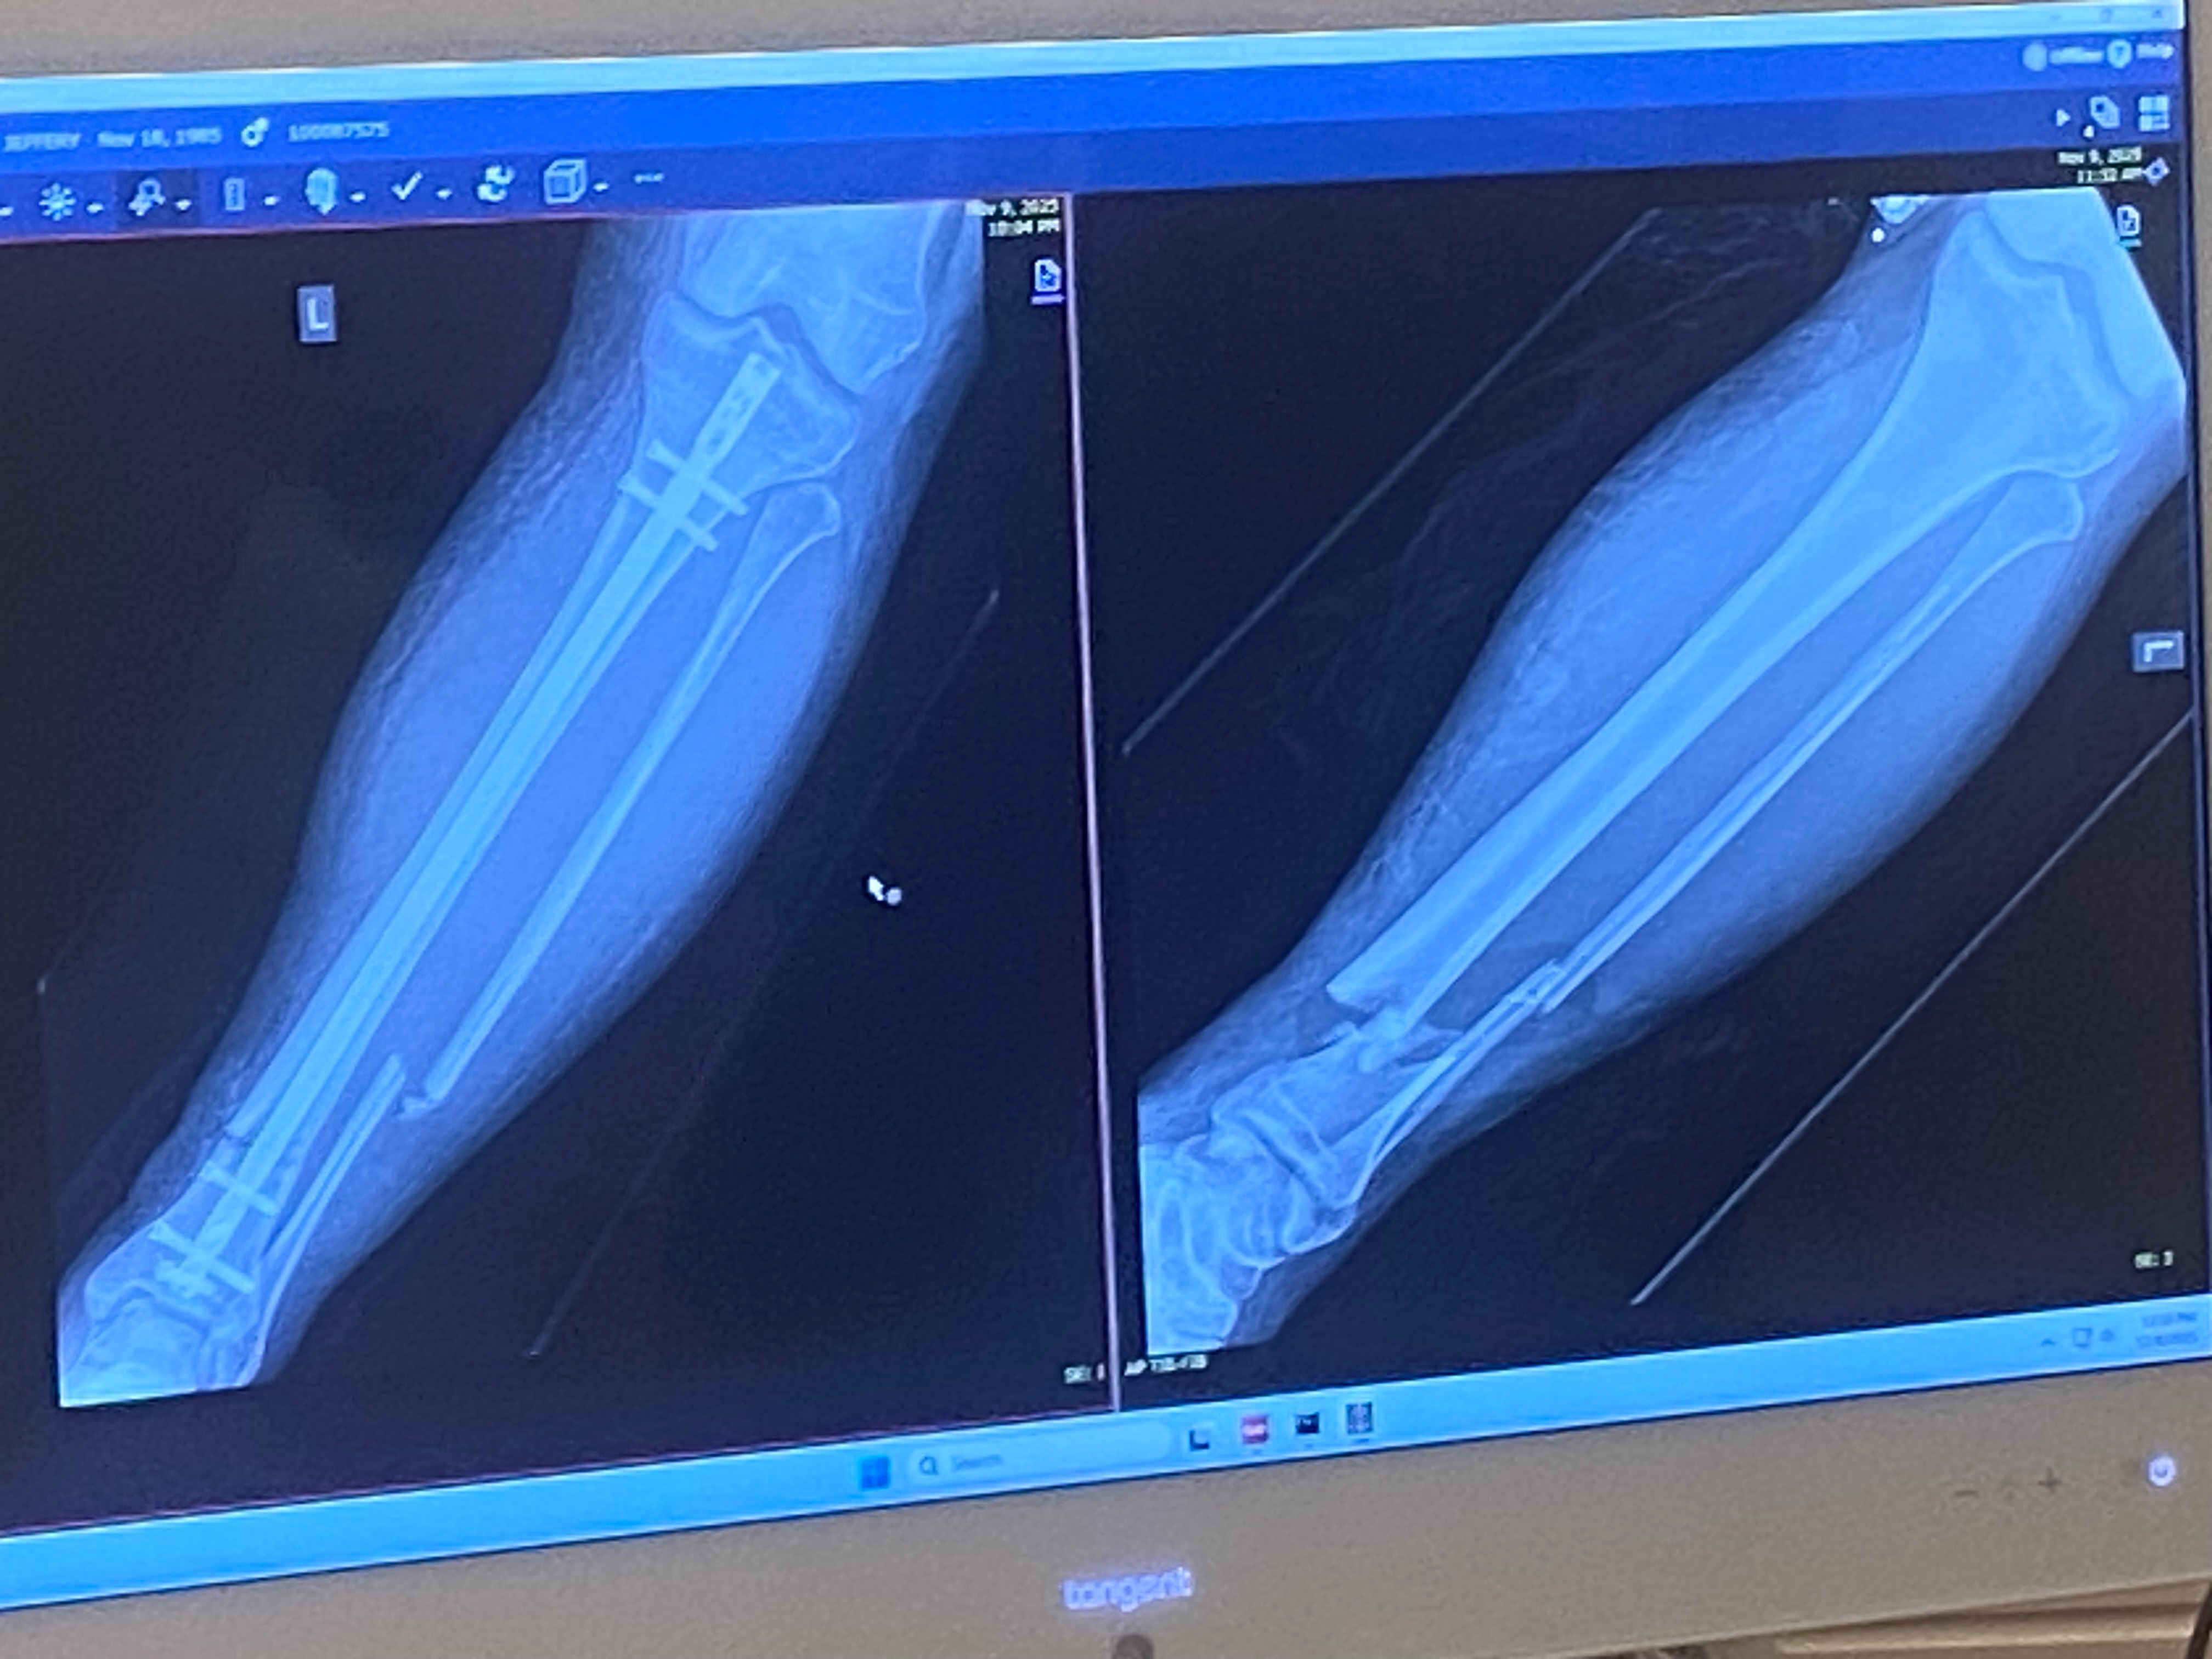

He had a broken tibia which was replaced with titanium hardware. He is unable to work for an unknown amount of time as his job is all standing and walking.